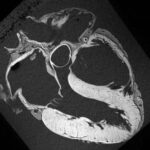

BRAIN MRI

A brain MRI is commonly used to investigate symptoms such as headaches, dizziness, seizures and can help detect conditions like tumours, strokes, inflammation, and multiple sclerosis.